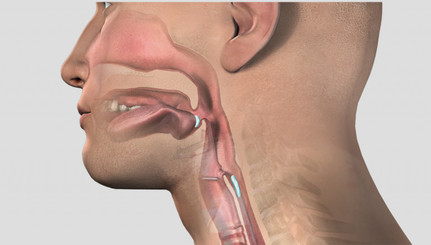

Aerodigestive and Respiratory Changes Post Tracheostomy: A Comprehensive Review

Tracheostomy: Procedures, Timing and Tubes

How You Breathe Matters: Swallowing Safely

Swallow Function: Passy Muir® Valve Use for Evaluation & Rehabilitation